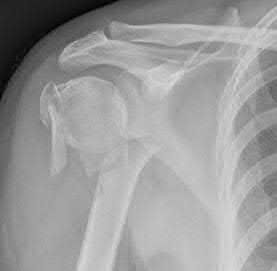

Question 12

A 55-year-old patient presents with a slowly enlarging, painful mass in the proximal humerus.

Biopsy reveals a hyaline cartilage matrix with cellular atypia, confirming a diagnosis of central conventional chondrosarcoma. Which of the following genetic mutations is most frequently identified in this specific tumor?

Explanation

Mutations in the isocitrate dehydrogenase genes, IDH1 and IDH2, are found in up to 50-60% of central conventional chondrosarcomas and enchondromas. EXT1 and EXT2 mutations are characteristic of multiple hereditary exostoses (osteochondromas). GNAS mutations are seen in fibrous dysplasia. TP53 and RB1 mutations are hallmark aberrations in osteosarcoma.